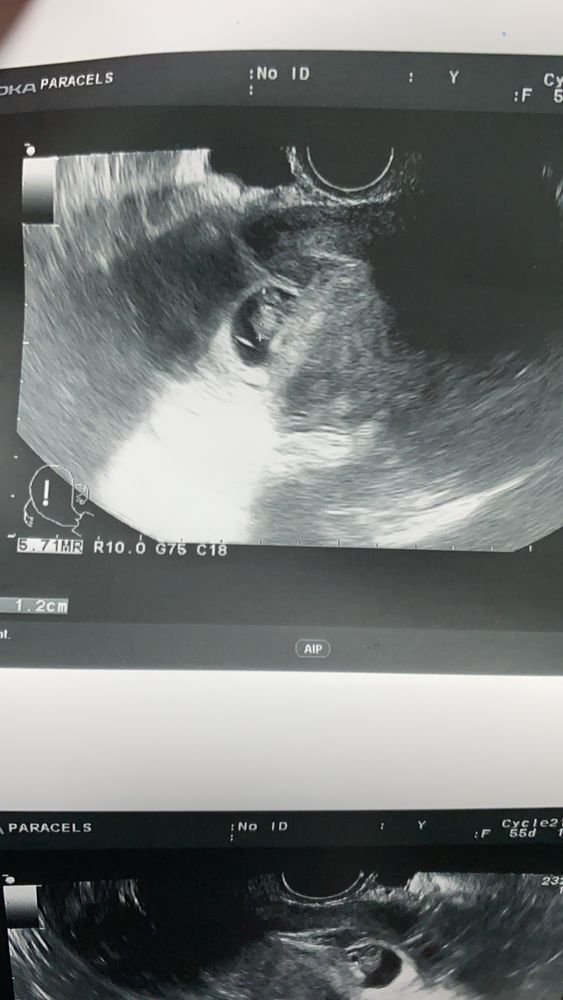

Узи 7-8 нед